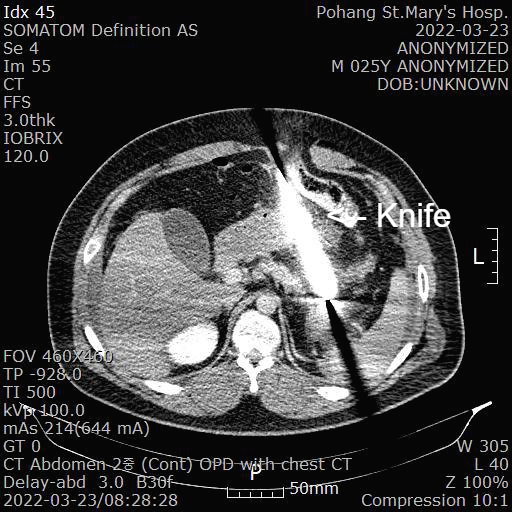

[복부 CT 판독]

1. stab wound at epigatrium by knife

2. dissection of t-colon with penetrating injury of t-mesocolon and upper jejunal mesentery

-- result in pneumohemoperitoneum

-- herniated t-colon distal loop and omental fat

-- with ongoing bleeding at mesentery

3. limited evaluation for pancreas tail injury due to strong beam-hardening artifacts

복강내에 흰색으로 보이는 부분이 칼이고 금속인 경우 CT를 찍으면 왜곡되어서 좀더 크게 보입니다.

칼로 인해 췌장 꼬리쪽 손상이 있고 대장도 칼에 의해 천공된 소견이 보입니다.